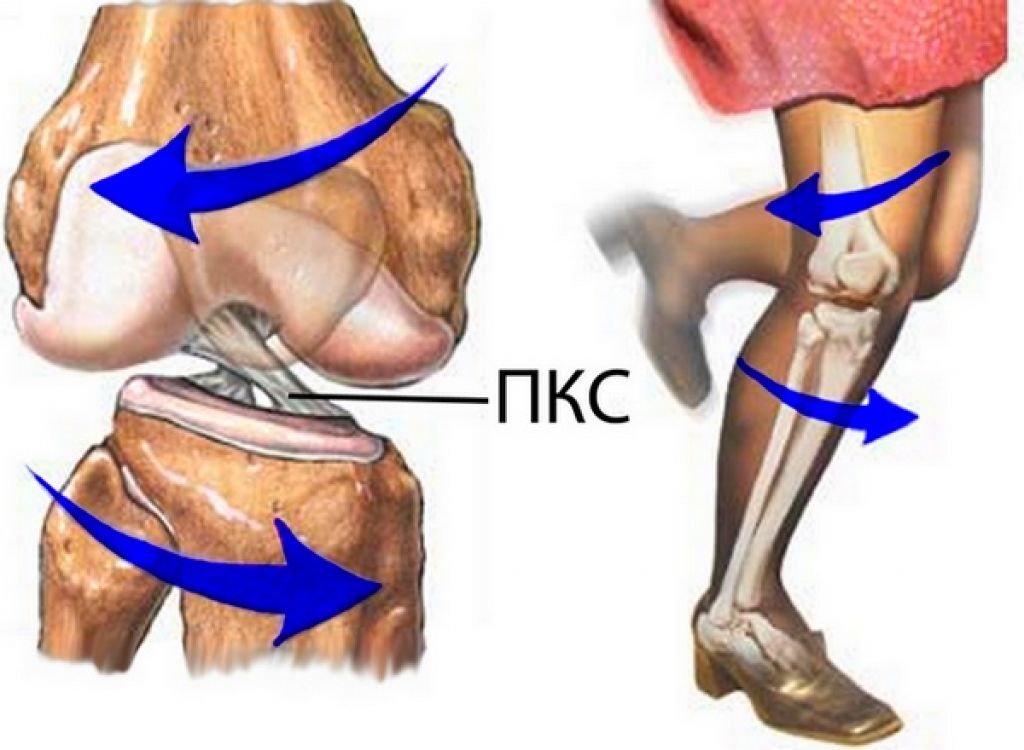

Пластика ПКС (артроскопия)